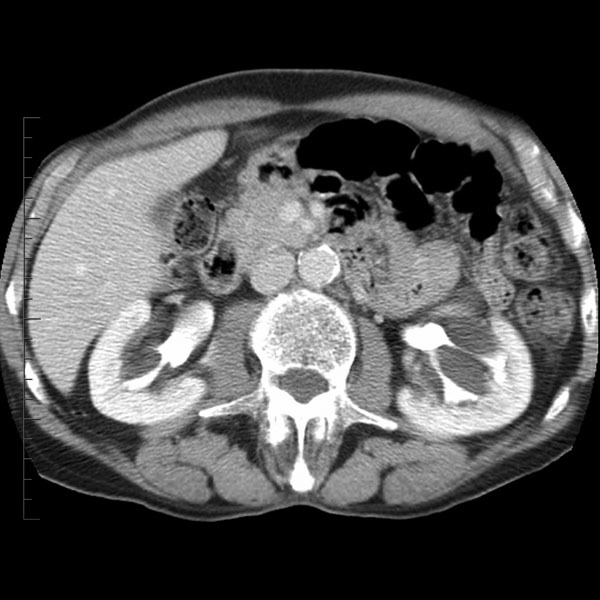

Angiomyolipoma (Aml)

Case courtesy of Dr Behrang Amini, Radiopaedia.org, rID: 35925

Axial CT through the kidneys shows a fat-attenuation lesion in the left kidney with a perirenal collection, most likely blood. This is consistent with a bleeding angiomyolipoma.